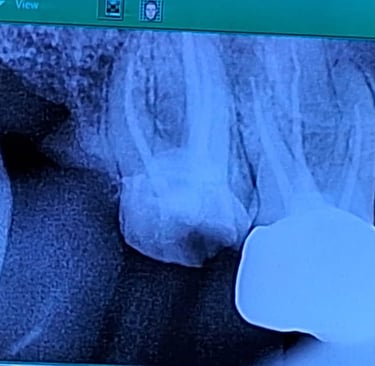

Single Sitting RCT

RCT is done in one visit, usually when the infection isn’t severe. It includes cleaning, shaping, disinfecting, and sealing the canal, followed by final restoration.